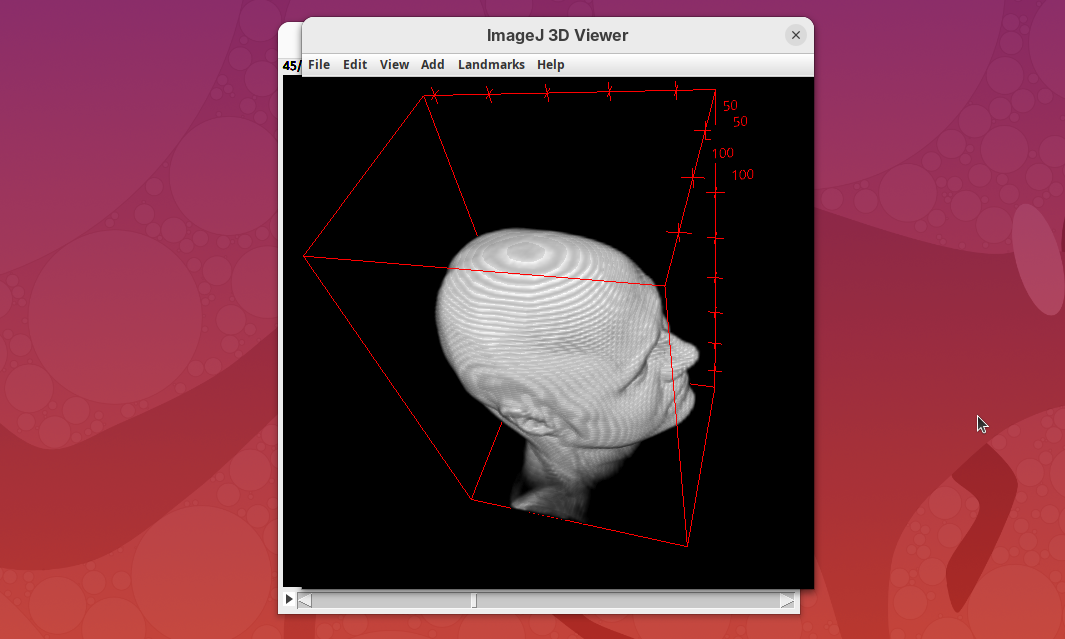

Cropping

Another useful 3Dscript option is the ability to crop the bounding box to show the inside of the sample. We can do it in the XYZ directions or in the near/far axis, defined from the user point of view.

- Set the Z range minimum value to

60(you can also drag the slider) to slice the sample through the Z axis.

- Now rotate the sample to see the cropped region from other angles.

- Set the Y range

minto125and rotate around.

- Finally, reset the position and cropping parameters and set the Near/Far minimum to

0and move the sample around to see the dynamic reslice of the sample with this cropping parameter.

- Reset transformations and cropping parameters.

You can also define if the bounding box or the scale bar will be visible (enabled by default).